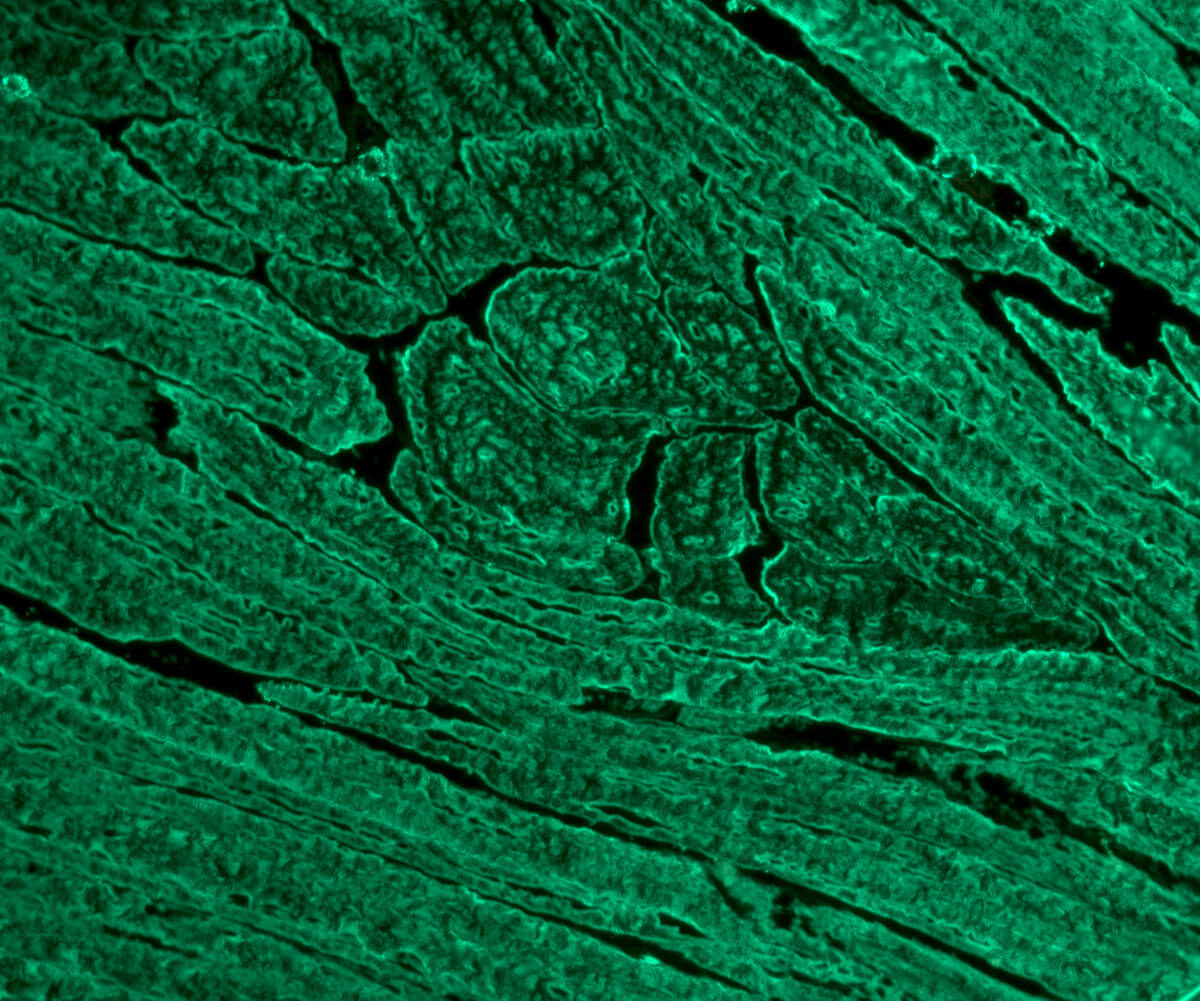

Objektträger beschichtet mit Skelettmuskulatur-Gewebeschnitten (Ratte) zum Nachweis von Antikörpern gegen Skelettmuskulatur aus Serum oder Plasma mittels Immunfluoreszenz.